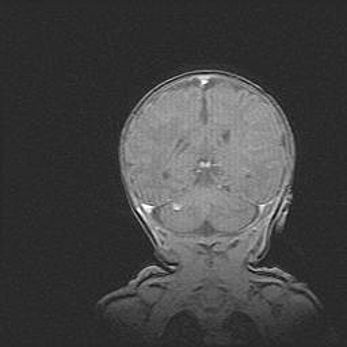

Открытая гидроцефалия.

Возраст: 9 месяцев 12 дней

Вес: 6800 г

Пол: мужской

Окружность головы: 41,5 см

Срок гестации: 28 недель

Гидроцефалия головного мозга у новорожденных имеет характерный признак: опережающий рост окружности головы приводит к визуально хорошо определяемой гидроцефальной форме сильно увеличенного в объёме черепа. Детские неврологи определяют следующие симптомы гидроцефалии у грудничков: выбухающий напряжённый родничок, частое запрокидывание головы, смещение глазных яблок к низу.